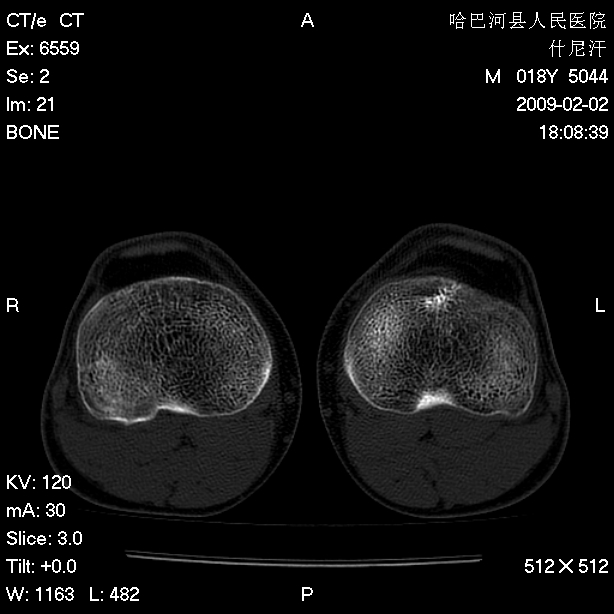

标题: CT17889:外伤后右膝关节反复疼痛3年余 [打印本页]

标题: CT17889:外伤后右膝关节反复疼痛3年余

ct未见明显异常。关节腔未见明显积液,半月板未见明显撕裂。但最好还是mri看看韧带及半月板情况。